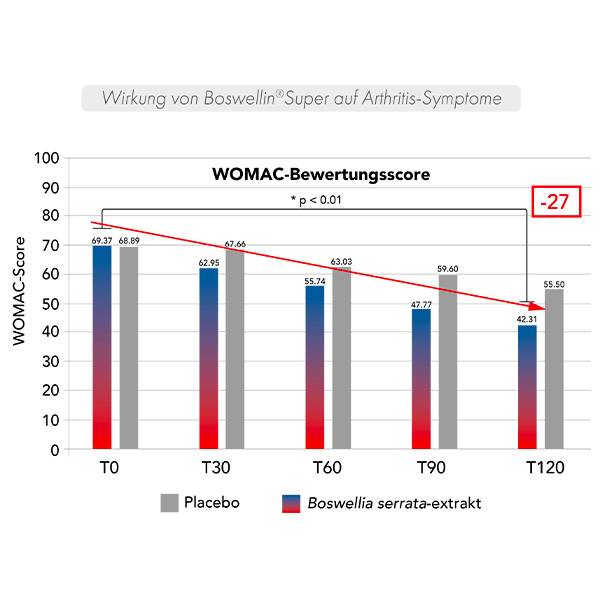

Eine kontrollierte, doppelblinde, placebo-kontrollierte klinische Studie mit 48 Personen, bei denen eine Osteoarthritis im Knie diagnostiziert wurde, wurde 120 Tage lang durchgeführt.

Die Bewertung der mit Osteoarthritis verbundenen Symptome erfolgte über einen Fragebogen bei den Teilnehmern (WOMAC**).

Die Arthritis-Symptome nehmen ab 30 Tagen bis zu 120 Tagen allmählich ab.

**WOMAC (Western Ontario and Mc Master Universities Arthritis Index) mesure la douleur articulaire et la fonction articulaire dans la vie quotidienne.